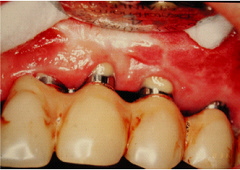

- 歯周病が進行しやすくなる可能性がある。